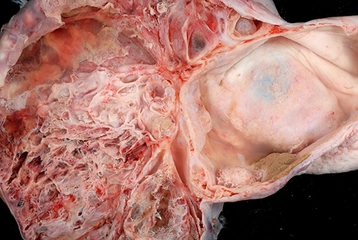

Akciğer tümörü, akciğerlerde anormal hücrelerin kontrolsüz bir şekilde büyümesiyle ortaya çıkan bir kanser türüdür. Bu tümörler, malign (kötü huylu) ve benign (iyi huylu) olarak iki gruba ayrılabilir. Malign tümörler hayati tehdit oluştururken, benign tümörler genellikle daha az tehlikeli olup tedavi edilmesi gereken durumlar arasında yer alır. Akciğer kanseri, dünya genelinde en yaygın kanser türlerinden biridir ve her yıl milyonlarca insanı etkilemektedir. Akciğer Tümörlerinin BelirtileriAkciğer tümörlerinin belirtileri, tümörün büyüklüğüne, yerine ve gelişim sürecine bağlı olarak değişiklik gösterebilir. Genel olarak görülen belirtiler şunlardır:

Tedavi YöntemleriAkciğer tümörlerinin tedavisi, tümörün tipi, evresi ve hastanın genel sağlık durumu gibi faktörlere bağlı olarak değişiklik gösterir. Genel tedavi yöntemleri şunlardır: